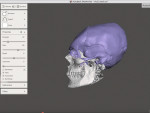

In this first workflow, a Mayan skull inspired by their craniofacial plastic criteria will be recreated. First, the acquisition of a skull is made by means of a CBCT (iCat™ FLX V10, Kavo Dental, kavo.com). The result is a DICOM file that contains all the necessary information in the form of pixels in gradual gradation in Hounsfield units. The less luminous pixels correspond to empty spaces like air, while the luminous pixels correspond to hard tissues like bone and teeth. The reconstruction software makes it possible to visualize the result in the form of a 3D object. By choosing the appropriate window, it is possible to hide the soft tissues and let only the mineralized tissues appear. A massive face with a fine resolution is obtained (Figure 3). The result obtained is exported in STL format for easy manipulation with software programs.

In a second step, modifications are made virtually. With a mouse click, the frontal bone may be flattened to lengthen the occipital bone and pull the parietal bones upward, while the cranial volume is maintained equally (Figure 4). All of these changes are made by computer, and the operator is able to view the final result immediately. The third step is to print the object in 3D. The computer project is exported in STL format (Figure 5) to be sent to a 3D printer (Solflex 650, Voco, voco.dental/us). A transparent resin (V-Print ortho, Voco) was used to produce a luminous artifact resembling a crystal skull: a Mayan skull printed in 3D (Figure 6).

In today's contemporary clinical practice, this technology is well suited to craniofacial orthopedics. Orthodontists and maxillofacial surgeons can work finely on their clinical cases and perform simulations ranging from simple 3D visualization on a computer to a 3D-printed object. Whether in the case of Angle Class III malocclusion or facial asymmetry, patients can now see and even touch what their face will look like after treatment.13